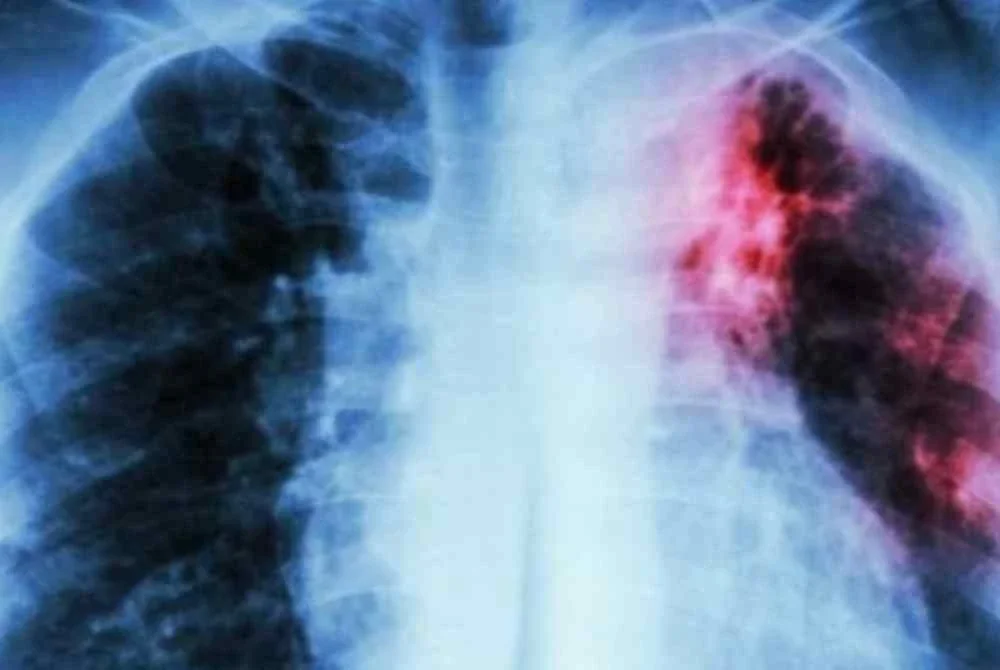

BATUK berpanjangan, peluh malam dan penurunan berat badan tanpa sebab mungkin kelihatan remeh, namun ia berpotensi menjadi petanda awal penyakit tuberkulosis atau tibi, iaitu sejenis penyakit berjangkit yang kini membimbangkan di negara ini.

Angka ratusan di beberapa buah negeri itu agak membimbangkan apatah lagi kesan penyakit tersebut bukan sahaja menjejaskan paru-paru, malah boleh merebak ke organ lain sekiranya tidak dirawat dengan segera.

Lebih risau apabila tibi boleh membawa maut jika pesakit gagal mendapatkan rawatan awal atau tidak mematuhi tempoh rawatan yang ditetapkan.